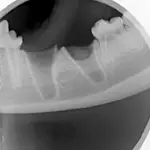

Step 9

Obtain a postoperative radiograph to verify that the entire tooth was extracted, and document the condition of the mandible following the extraction.